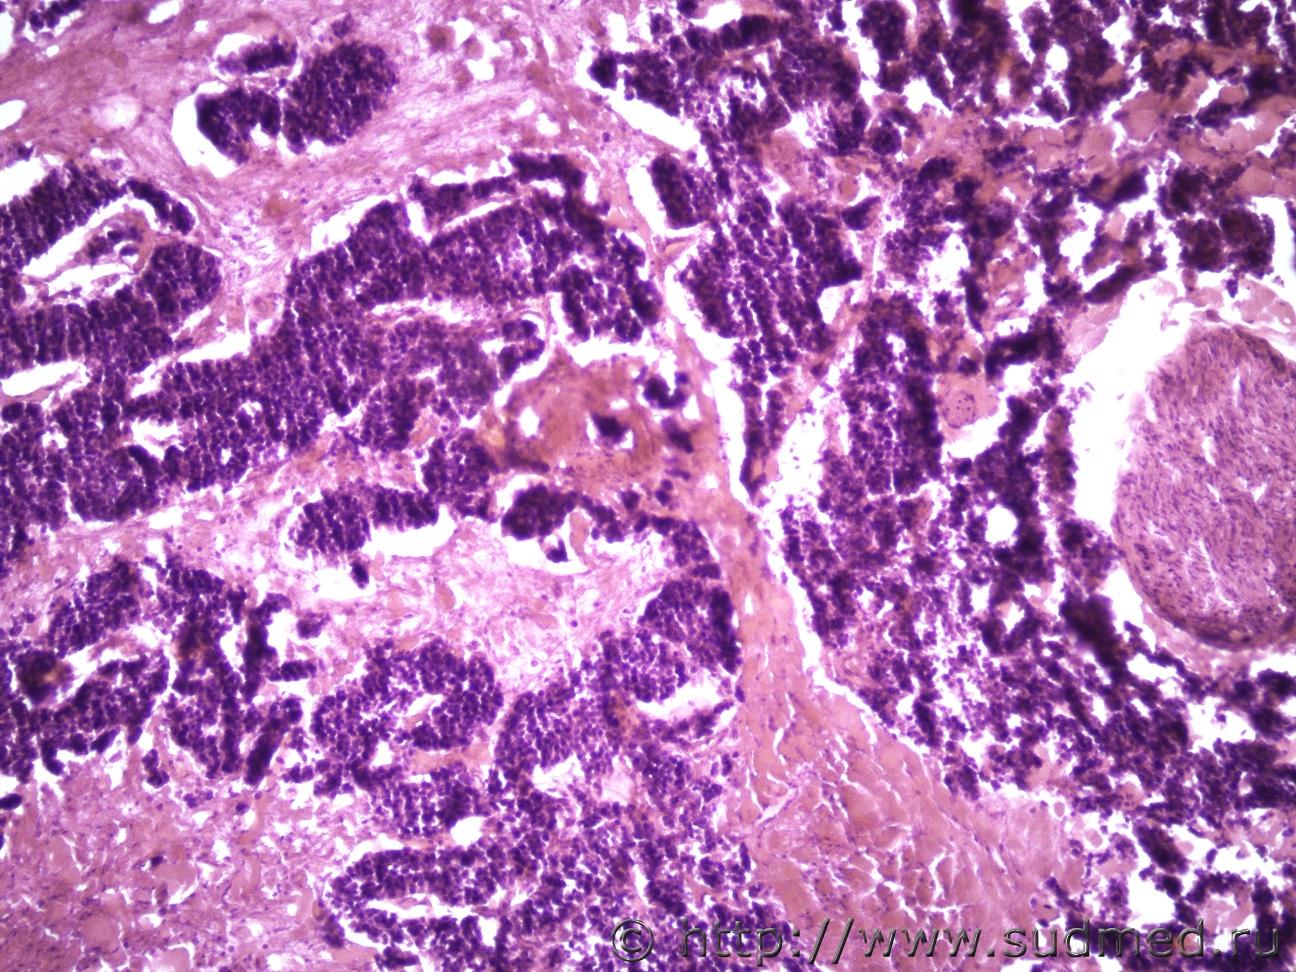

Ув. коллеги и снова здравствуйте. Как всегда опухоль. Макро- опухоль поджелудочной железы с прорастанием в окружающую клетчатку с метастазами в перибронхиальные, перипортальные ЛУ, в прикорневые отделы легких, в стенку желчного пузыря, тонкого кишечника. Легкие Судебная медицина - Прикрепленное изображение Судебная медицина - Прикрепленное изображениеСудебная медицина - Прикрепленное изображениеСудебная медицина - Прикрепленное изображение, перибрЛУСудебная медицина - Прикрепленное изображение ПЖ Судебная медицина - Прикрепленное изображениеСудебная медицина - Прикрепленное изображение , печеньСудебная медицина - Прикрепленное изображение Судебная медицина - Прикрепленное изображение Судебная медицина - Прикрепленное изображение Судебная медицина - Прикрепленное изображение Судебная медицина - Прикрепленное изображение, тонк кишСудебная медицина - Прикрепленное изображение

Наиболее подходит нейроэндокринный рак

Спасибо, рассмотрю этот вариант. Я все думала может НД протоковая аденокарцинома или мелкоклеточный рак.

Солидарен.

Непохоже.